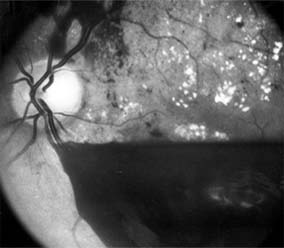

Figure 10-22

Figure 10-22: Late phase fluorescein angiogram shows hyperfluorescence typical of noncystoid diabetic macular edema.